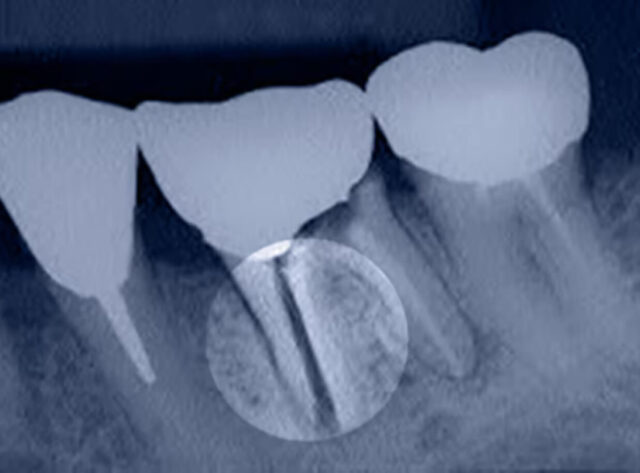

Another option is intraligamentary anesthesia, which is suitable for the extraction of teeth, both in the lower and upper jaw. The anesthetic medicine is injected into the periodontal ligament using a thin (0.3 mm) needle. Since a very high pressure is required, we use a special syringe (e.g., Citoject syringe or Soft-Ject syringe). Each tooth root requires at least one puncture. The anesthetic solution penetrates the tooth ligament to the tooth root’s tip and numbs the nerve fibers entering the pulp. With intraligamentary anesthesia, less anesthetic is administered to the tooth as a whole, which is especially important for patients with a high risk of hypertension.